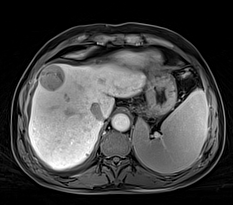

体部成像 --- GRASP动态增强

自由呼吸,无需屏气

连续扫描,不错过最佳对比

实例展示

磁共振矩阵怎么计算【重磅】新一代智慧型生命感知磁共振——MAGNETOM Vida, 成功落户中大放射并全面投入使用!!!_https://www.jmylbn.com_新闻资讯_第27张

肝癌治疗前后对比,GRASP-VIBE动态增强---自由呼吸状态下连续高时间分辨率成像